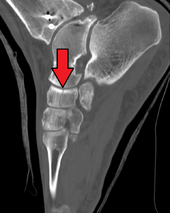

The navicular bone in humans is located on the medial side of the foot, and articulates proximally with the talus, distally with the three cuneiform bones, and laterally with the cuboid.

The human navicular is not a commonly broken bone.